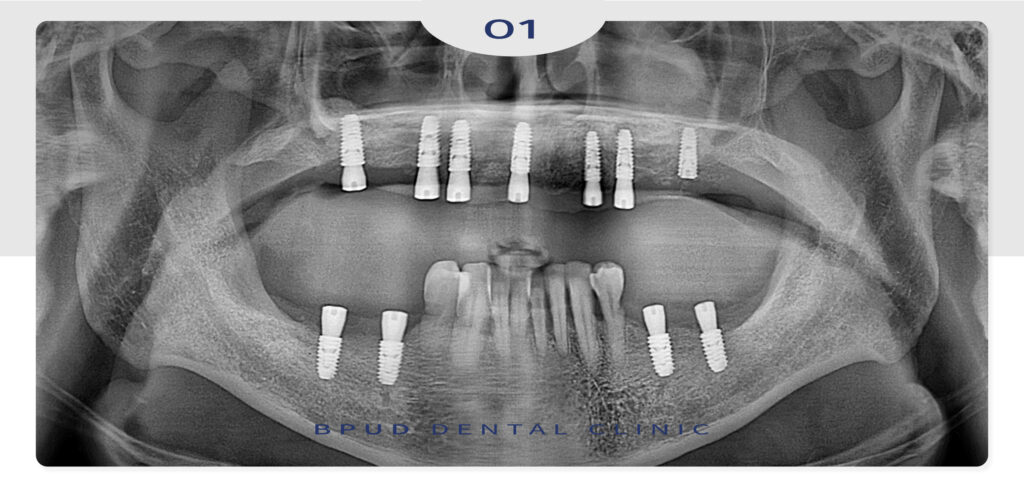

전체 골격성 3급 부정교합이 있으셨고

상악의 치조골이 과도하게 흡수되어

일반 보철 진행 시 너무 앞으로 튀어나올 수 있는

상황에서 양쪽 상악동 거상술 및 앞니 골이식술을

동반하여 전체 임플란트를 시행하기로 하였습니다.

상악은 적은 비용으로 7개를 식립하기로 하였고

양쪽 상악동 거상술 및 위축된 앞니 치조제 부위

뼈를 이식하였고

아래쪽은 양쪽에 2개씩 식립을 하였는데

골격성 3급 부정교합으로 인해 대합치 관계를

고려하여 일반적인 간격보다 넓게 식립을 하였습니다.